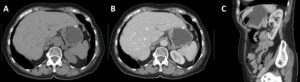

The CT scan images were reviewed and an hyperdense image in the topography of the gastric SEL was identified (Figure 3).

Figure 3. CT scan: stomach distended with water with normal thickness wall, and an hyperdense image near the gastric wall (2A – axial view; 2B – axial view contrast-enhanced; 2C – sagittal view).